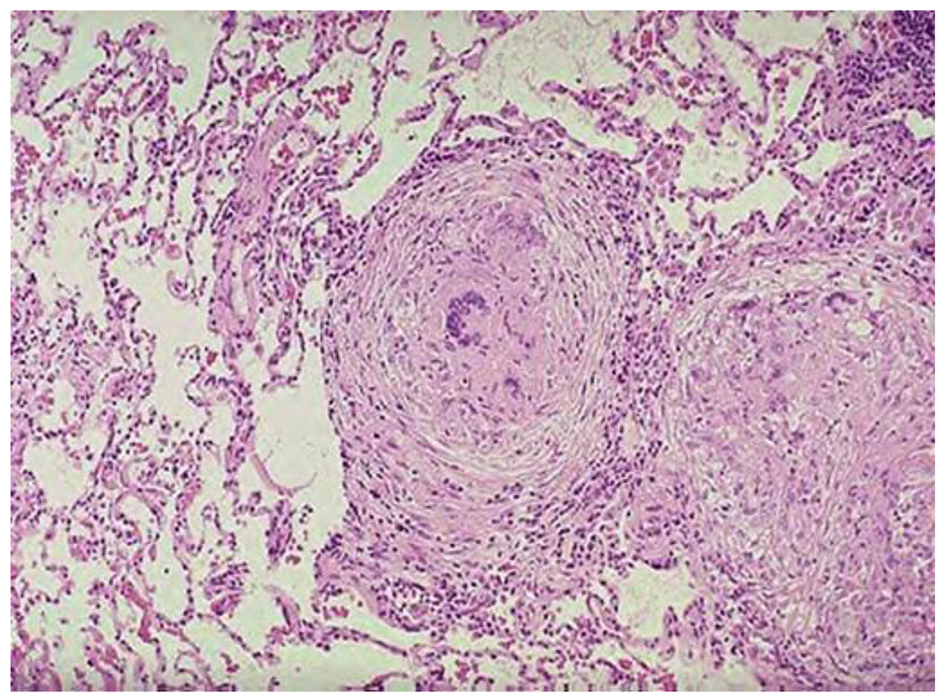

Карнификация Легкого: Микропрепараты и Диагностика

Раздел: Калейдоскоп образов